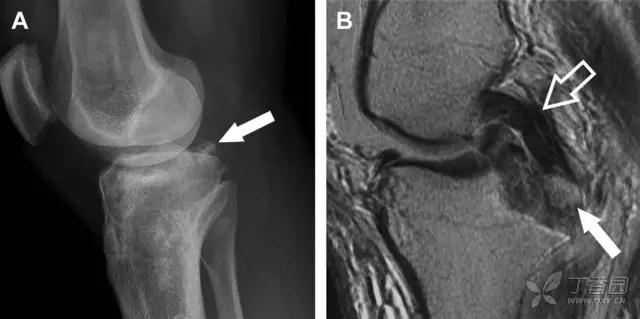

11 Segond 骨折

Segond 骨折是发生在胫骨平台外侧的垂直撕脱性骨折(图 4)。这种骨折在前后位 X 线片上显示最佳。

屈曲位时膝关节受到内旋*力暴**作用,导致皮质骨撕脱性骨折,这种骨折常发生在运动员身上。常引起股骨内髁和胫骨平台后内侧骨挫伤,75%~100% 的患者伴前交叉韧带断裂,33% 的患者伴外侧半月板损伤。

图 4 一位足球运动员的 Segond 骨折

A 正位片示关节线下方胫骨外侧皮质撕脱(箭头)。B MRI 冠状位 T1 加权像示附着于髂胫带的骨折碎片(空箭头)。